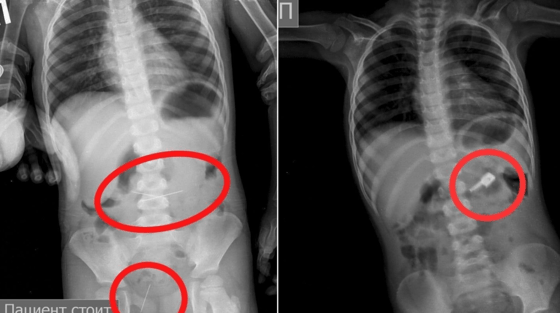

Aniqlanishicha, 3 yoshli bolaning onasi uni kasalxonaga olib kelgan. Rentgenda uning oshqozonida tikuv ignalari borligi koʻrinib, hammasi boʻlib kichkina bemor 4 ta ignani yutib yuborganligi maʼlum boʻlgan.

Shifokorlar bir necha kun davomida endoskopik asbob-uskunalar yordamida jarrohlik amaliyotisiz ignalarni olib tashlashgan.